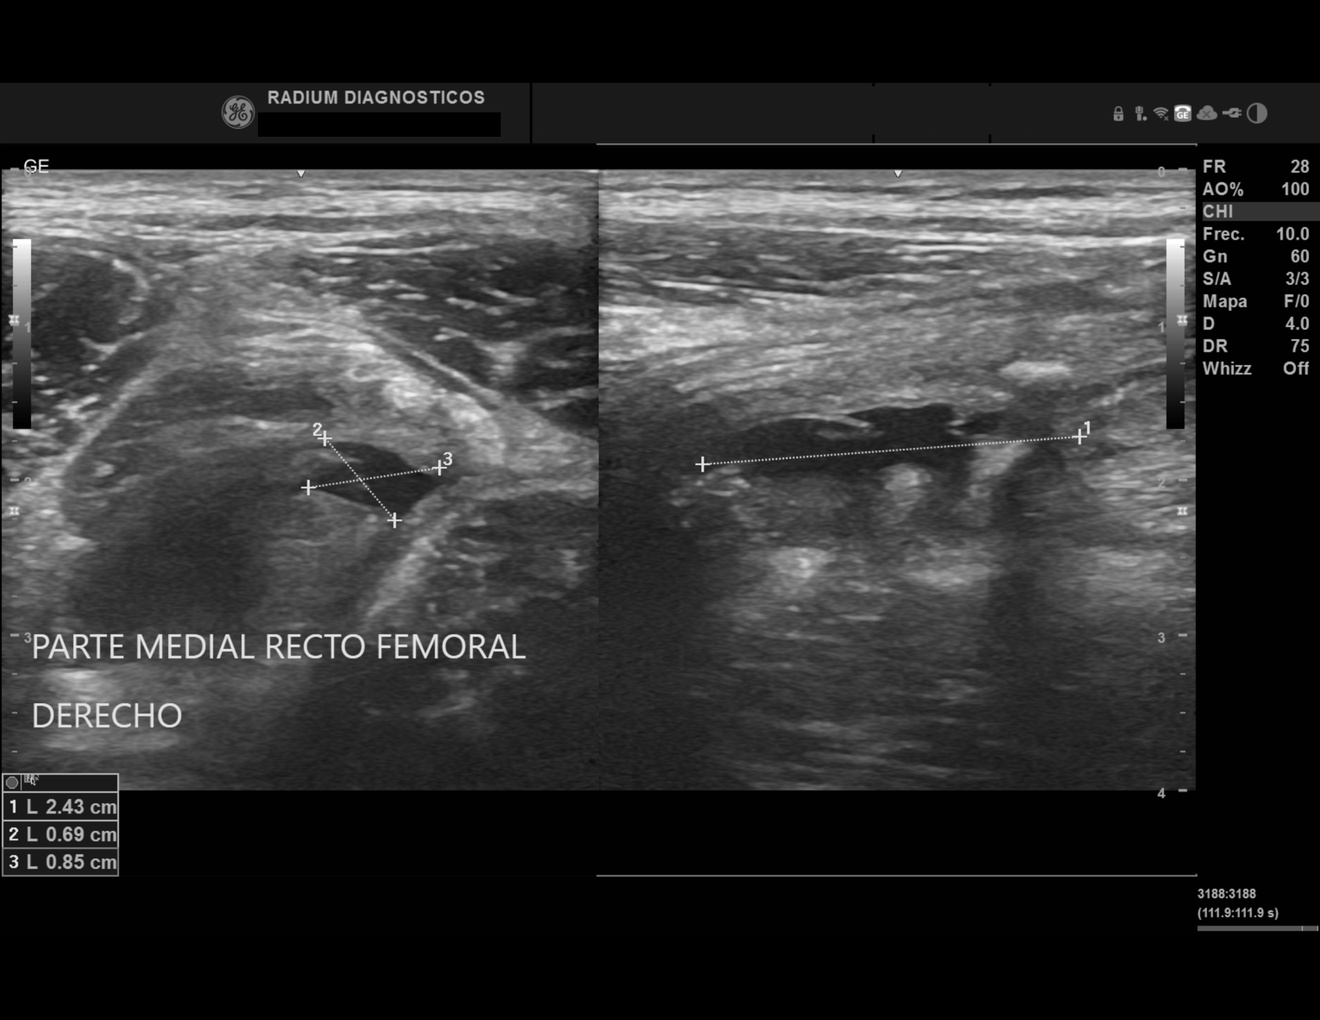

En centro de Imagen Radium ofrecemos estudios de Radiología e Imagen Médica de alta precisión a un precio justo, con equipos de última generación.

Imágenes de Alta Precisión.